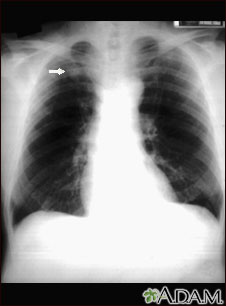

Esta radiografía muestra una sola lesión (nódulo pulmonar) en la parte superior del pulmón derecho (se puede observar como un área clara al lado izquierdo de la imagen). El nódulo tiene bordes bien definidos y es uniforme en cuanto a densidad. La tuberculosis (TBC) y otras enfermedades pueden ocasionar esta clase de lesión.